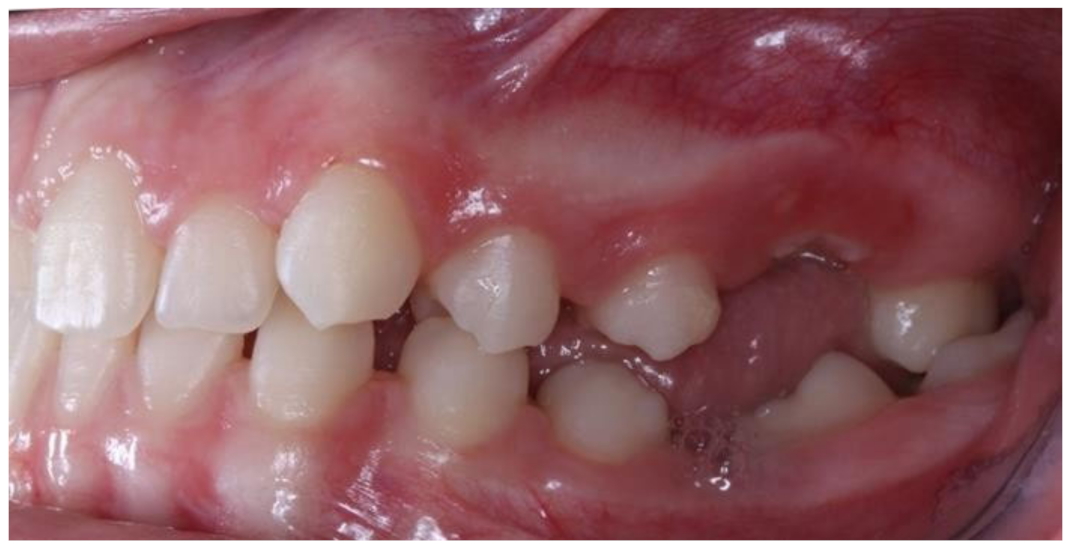

Figure 6.

Left photo of the same female patient depicted in Figure 5.

Open bite is present at the right posterior segment due to the impaction of the upper and lower left first molars.

Figure 5 and Figure 6 present a PFE case of a 17-year-old female patient referred to the Orthodontic Clinic of the Dental School of the National and Kapodistrian University of Athens, Greece. Clinical examination showed a posterior open bite on the right segment, as well as infraoccluded left upper and lower first molars. The patient’s orthopantomography shows no visible PDL of the right upper and lower first molars or the teeth distally related to them.